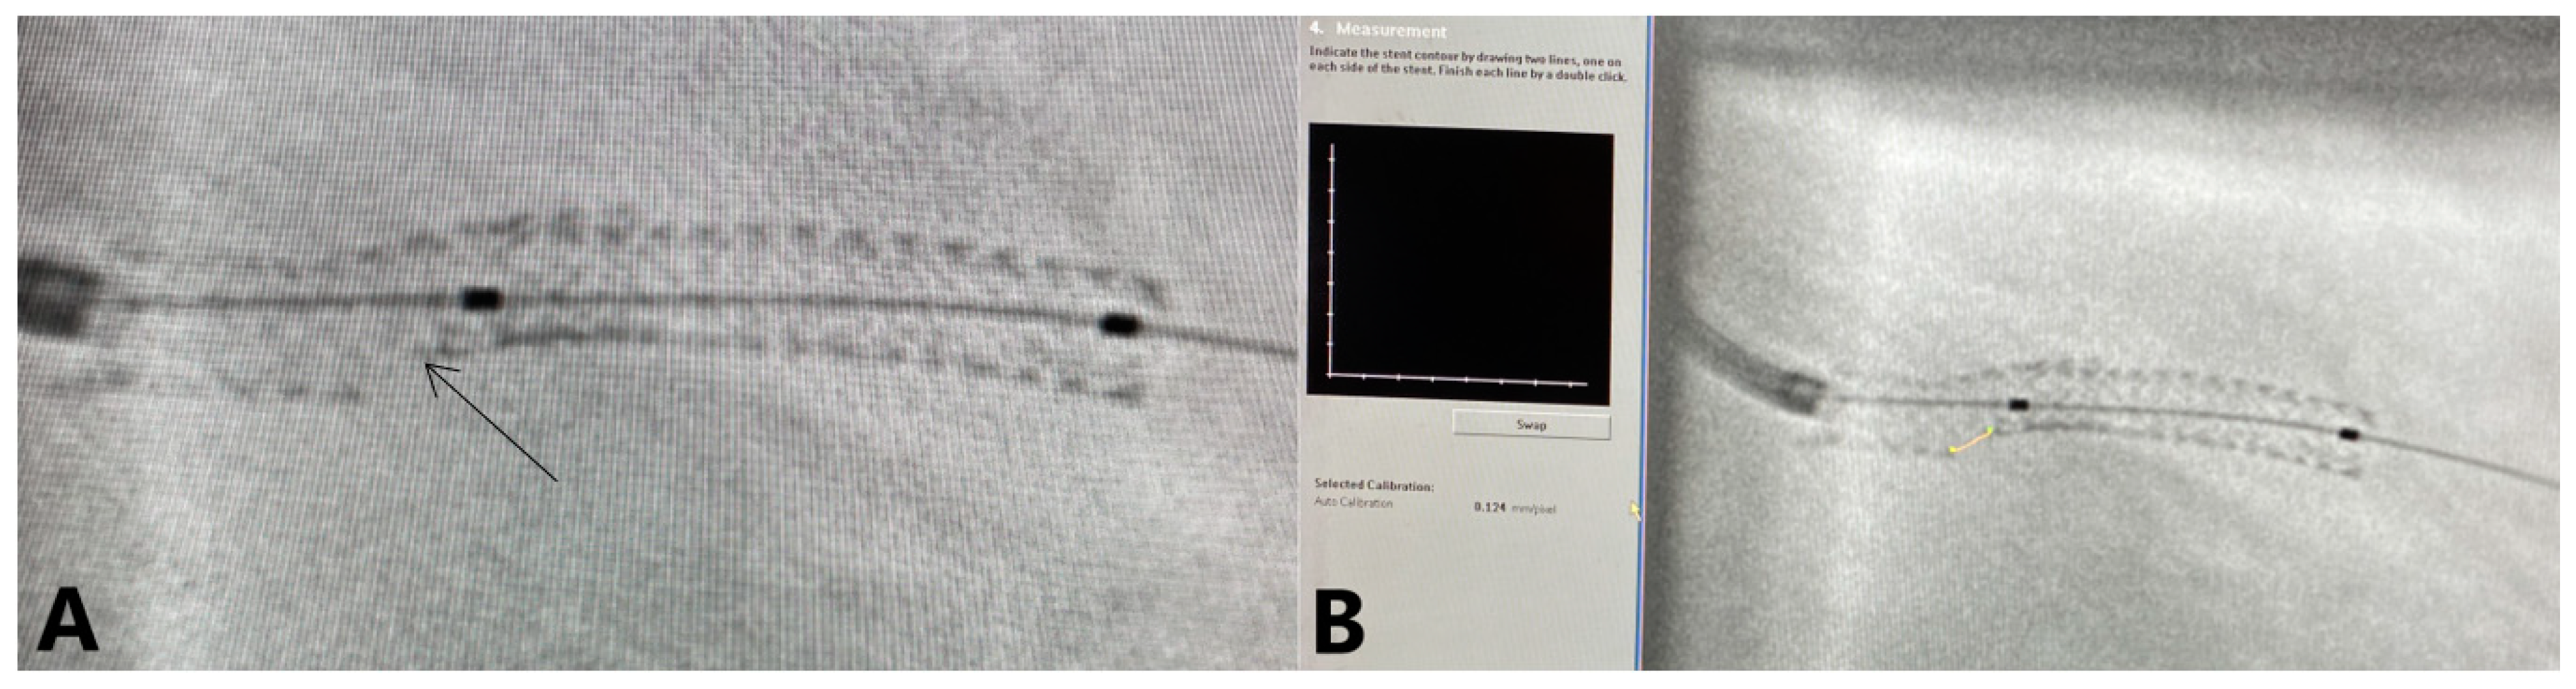

| SESBL | stent enhancement side branch length |

- Silva, J.D.; Carrillo, X.; Salvatella, N.; Fernandez-Nofrerias, E.; Rodriguez-Leor, O.; Mauri, J.; Bayes-Genis, A. The utility of stent enhancement to guide percutaneous coronary intervention for bifurcation lesions. EuroIntervention 2013, 9, 968–974. [Google Scholar] [CrossRef]

- Biscaglia, S.; Tumscitz, C.; Tebaldi, M.; Andrenacci, E.; Pavasini, R.; Campo, G.; Ferrari, R. Enhanced stent visualization systems during PCI: A case series and review of literature. J. Cardiol. Cases. 2015, 12, 1–5. [Google Scholar] [CrossRef]

- Figini, F.; Louvard, Y.; Sheiban, I. Stent Enhancement during Percutaneous Coronary Intervention: Current Role, Technical Tips and Case Examples. Cardiovasc. Revasc. Med. 2020, 21, 137–143. [Google Scholar] [CrossRef] [PubMed]